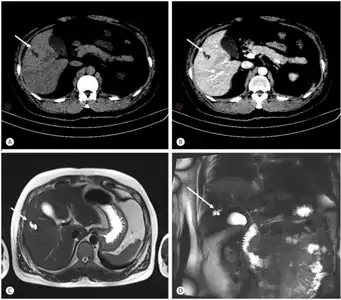

Bileduct dilatation in segment 5 arrow a,b) CT, c) MRI, d) MRCP -

Modern imaging techniques allow the diagnosis to be made more easily and without invasive imaging of the biliary tree.[9] Commonly, the disease is limited to the left lobe of the liver. Images taken by CT scan, X-ray, or MRI show enlarged intrahepatic (in the liver) bile ducts due to ectasia. Using an ultrasound, tubular dilation of the bile ducts can be seen. On a CT scan, Caroli disease can be observed by noting the many fluid-filled, tubular structures extending to the liver.[4] A high-contrast CT must be used to distinguish the difference between stones and widened ducts. Bowel gas and digestive habits make it difficult to obtain a clear sonogram, so a CT scan is a good substitution. When the intrahepatic bile duct wall has protrusions, it is clearly seen as central dots or a linear streak.[10] Caroli disease is commonly diagnosed after this “central dot sign” is detected on a CT scan or ultrasound.[10] However, cholangiography is the best, and final, approach to show the enlarged bile ducts as a result of Caroli disease.